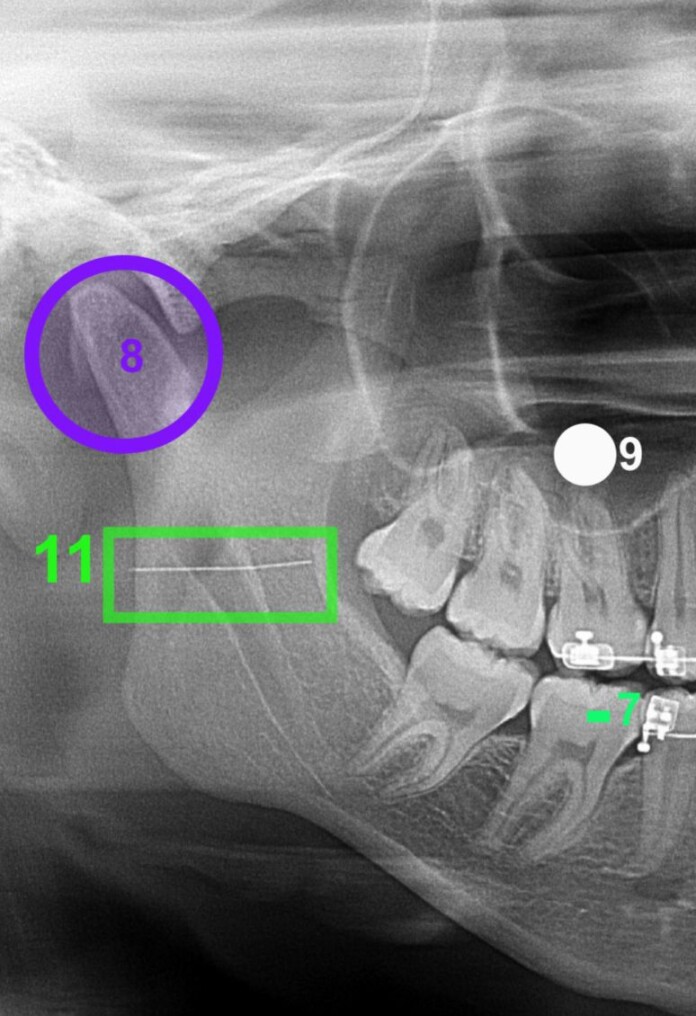

Exames de imagem realizados posteriormente confirmaram a presença do fragmento metálico no ramo mandibular. A criança passou por uma cirurgia em outra unidade especializada, mas o cirurgião responsável concluiu que a retirada do objeto representava risco, já que a profundidade poderia causar danos.

Após o procedimento, a orientação era de que fossem feitos exames trimestrais para monitorar a posição da agulha. Porém, segundo a família, o profissional responsável pelo atendimento inicial não assumiu os custos, obrigando-os a pagar pelos exames em uma clínica de radiologia da cidade.

Após o procedimento, a orientação era de que fossem feitos exames trimestrais para monitorar a posição da agulha: Foto/Reprodução